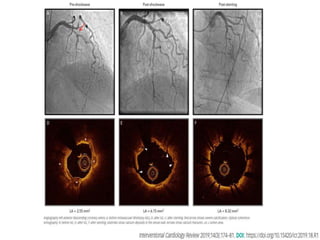

Heavily calcified vessel by OCT

Heavily calcified vesselby OCT • Arc >1800 • Length > 5 mm • Thickness > 0.5 mm